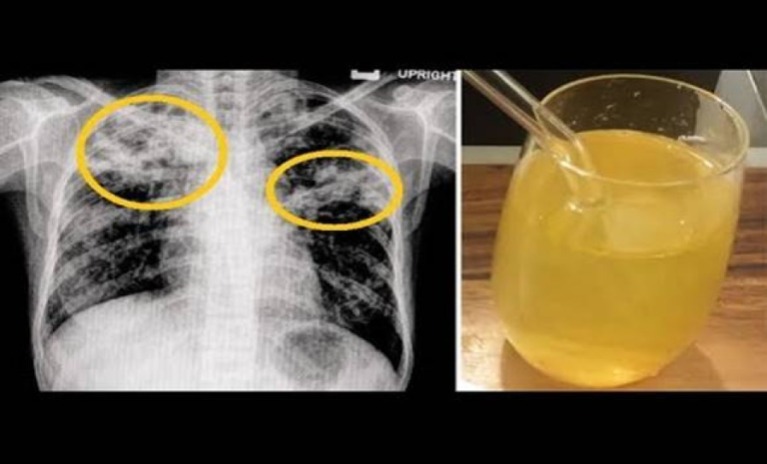

A köhögés és a nehézlégzés legfőbb oka fertőző légúti betegségek előfordulásakor a lerakódott váladék, amelyet a légutak nyálkahártyája termel. Ennek a váladéknak szerepe van a szennyezőanyagok, allergének és kórokozók csapdába ejtésében....